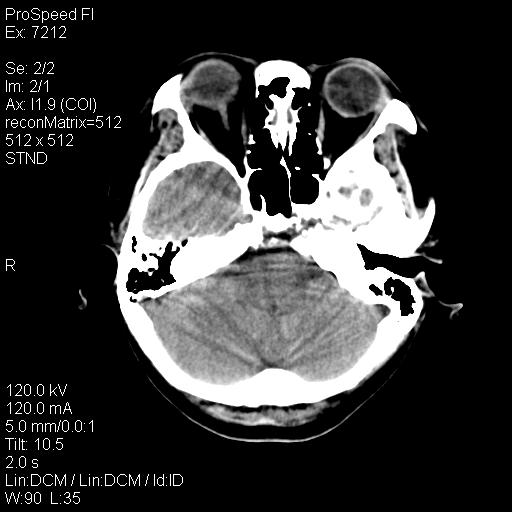

标题: CT18636:F 44Y,头痛三个月,左侧肢体麻木一周。临床诊断, [打印本页]

标题: CT18636:F 44Y,头痛三个月,左侧肢体麻木一周。临床诊断,

右额叶脑沟变浅,脑表面见新月形稍高密度影,考虑慢性硬膜下出血可能。